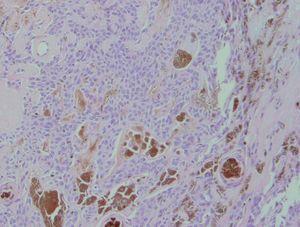

A la exploración se apreciaba una tumoración hiperpigmentada de 2 cm de diámetro, de consistencia firme, superficie lisa y bordes netos localizada en ingle derecha (fig. 1). El estudio histopatológico evidenció una tumoración sólida, dérmica, bien delimitada, pero no encapsulada, que no contactaba con la epidermis ni con la hipodermis (fig. 2). Estaba compuesta por células poligonales, ovoides o redondeadas, de límite bien definido y citoplasma amplio, con núcleos ovoides o redondeados, de cromatina fina, sin pleomorfismo significativo y con mitosis frecuentes. También se observaban células de características similares, aunque con citoplasmas claros. En el centro había áreas de fibrosis con abundante melanina (fig. 3) y en otras zonas se apreciaban cavidades pseudoglandulares que contenían mucina.

Fig. 3.--Células tumorales sin atipia ni mitosis, alguna estructura ductal y abundante melanina. (Hematoxilina-eosina, x200.)